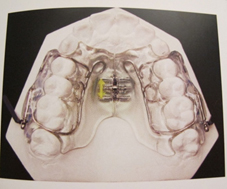

Les appareils d’expansion du maxillaire

Ils permettent d’élargir la mâchoire du haut (le maxillaire) chez un enfant en cours de croissance.

En fonction de l’importance de l’élargissement et de l’âge du patient, on peut utiliser différents outils :

Le disjoncteur

Fiche à télécharger : Conseils Disjoncteur